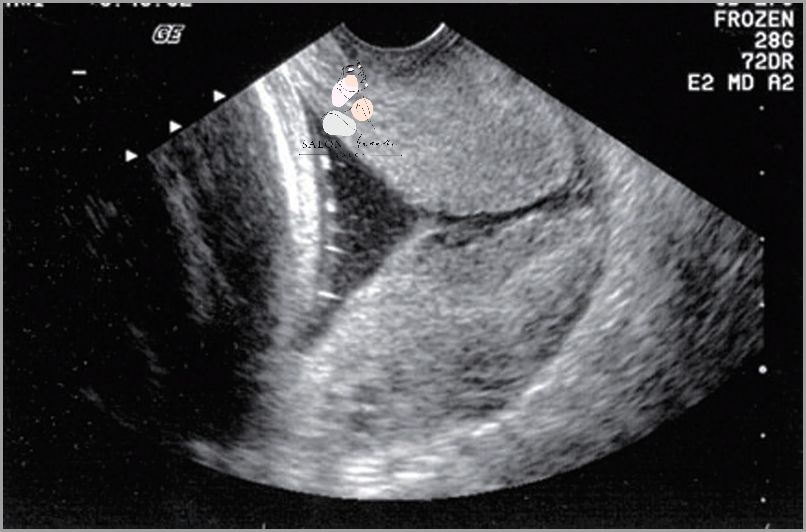

Skrócona szyjka macicy w ciąży jest jednym z najczęstszych problemów, jakie mogą wystąpić u kobiet w ciąży. Szyjka macicy skraca się w wyniku skurczów macicy, które są częścią normalnego procesu przygotowywania się do porodu. Choć skrócona szyjka macicy w ciąży może być niebezpieczna dla ciężarnej, lekarze mogą skutecznie ją leczyć. Leczenie może polegać na podawaniu leków, zmianie trybu życia lub hospitalizacji. Aby zapobiec skróceniu szyjki macicy w ciąży, kobiety w ciąży powinny unikać stresu, zapewnić sobie wystarczającą ilość snu i dostosować swoją dietę do zaleceń lekarza.

Skrócona szyjka macicy w ciąży jest jednym z najczęstszych powikłań ciąży i może prowadzić do poważnych komplikacji, takich jak przedwczesny poród lub nawet poronienie. Objawy skróconej szyjki macicy w ciąży mogą obejmować ból i podrażnienie szyjki macicy, ból i skurcze brzucha, plamienie lub krwawienie z pochwy, zmiany w wydzielinach z pochwy, i zawroty głowy.

W przypadku wystąpienia jakichkolwiek objawów skróconej szyjki macicy w ciąży, należy skontaktować się z lekarzem, aby uzyskać odpowiednią opiekę medyczną. Lekarz może zalecić monitorowanie szyjki macicy i leczenie farmakologiczne, aby zapobiec poronieniu.

Skrócona szyjka macicy w ciąży może być kontrolowana przez lekarza. Lekarz może stosować różne metody, aby poprawić długość szyjki macicy. Metody te obejmują leczenie farmakologiczne, zastrzyki i zabiegi chirurgiczne.